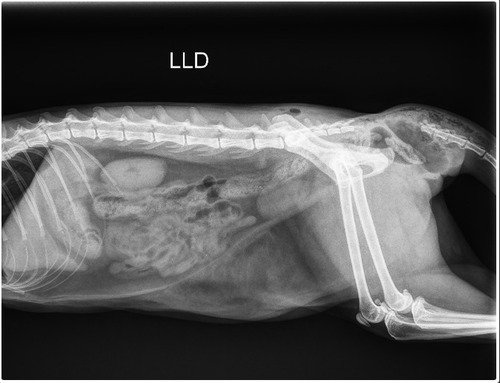

Após avaliação veterinária e exames, foi confirmado que a amputação é a única opção para aliviar a dor que ela sente e permitir que tenha uma vida digna e sem sofrimento. Infelizmente, os custos com cirurgia, exames, internação, medicações e pós-operatório são altos e estão além das minhas condições financeiras no momento.